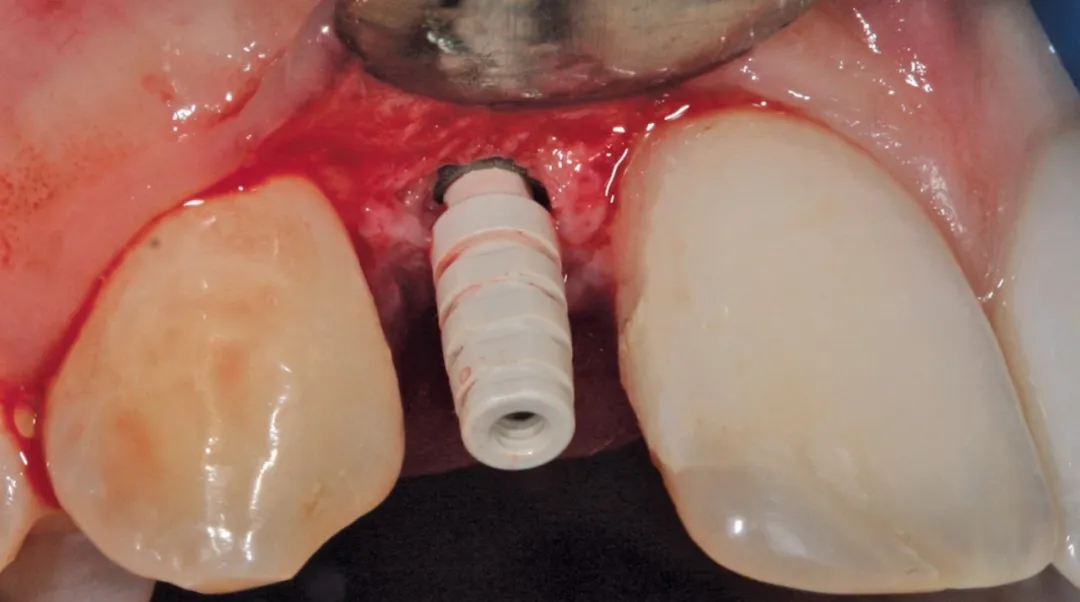

图 38 :拔牙后种植位点。

图 39 :种植体就位。